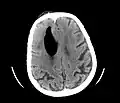

Pneumocephaly